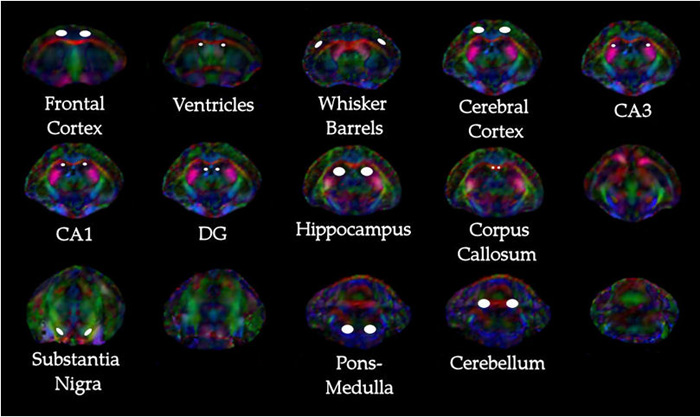

Hemispheric Regional Based Analysis of Diffusion Tensor Imaging

Fig 1. | Diffusion Tensor Imaging as Potential Biomarker of White

Clinical correlates of cerebral diffusion tensor imaging findings